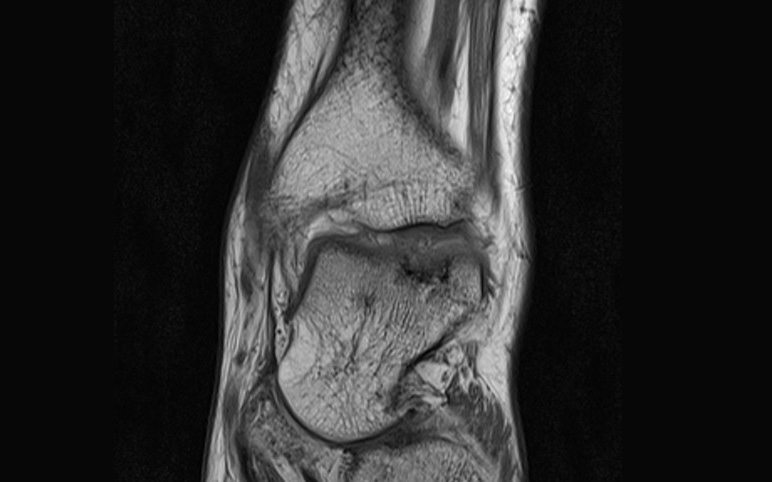

Badanie manualne nie jest w stanie jednoznacznie określić przyczyny dolegliwości. Konieczne jest wykonanie prześwietlenia RTG w projekcji przednio-tylnej, bocznej i celowanej na więzozrost piszczelowo-strzałkowy, jednak często w badaniu RTG nie widać odchyleń od normy. W przypadku podejrzenia złamania kostno-chrzęstnego konieczne jest badanie tomografii komputerowej lub rezonansu magnetycznego. Oba te badania są pomocne w zaplanowaniu leczenia.